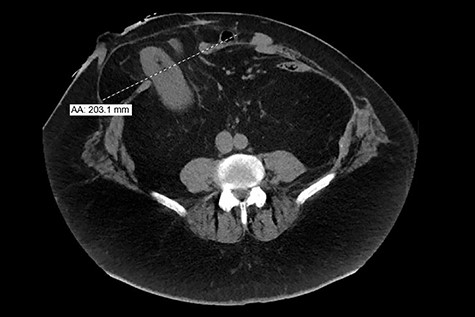

The patient’s past surgical history is very complicated. In February 2015, the patient presented for ischemic colitis with bowel perforation, requiring an exploratory laparotomy that resulted in a subtotal colectomy with end ileostomy. His hospital course was protracted due to wound infections and intra-abdominal abscesses. After 7 months, he presented for an ileostomy reversal and underwent a laparotomy with small bowel resection and ileocolic anastomosis. His hospital course was protracted once again due to an intra-abdominal anastomotic leak and multiple abdominopelvic abscesses. This resulted in a resection of his ileoproctostomy, multiple abdominal washouts, a small bowel resection and creation of an end-ileostomy. In 2016, the patient presented multiple times with a recurrent left retroperitoneal abscess along the posterior abdominal wall and underwent three open abdominal surgeries for incision and drainage. A computed tomography (CT) scan from November 2016 did not show any evidence of kidney herniation (Fig. 1).

Computed tomography (CT) image from 2016 shows the right kidney in normal anatomical position.